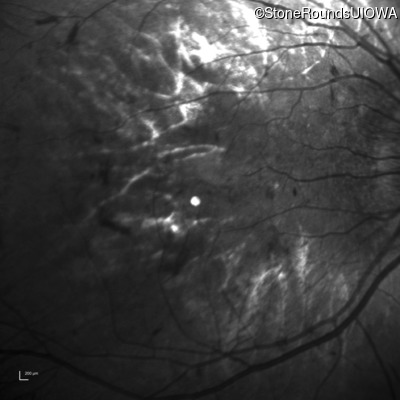

Infrared Fundus Photograph - Left - 5/160

Exemplar